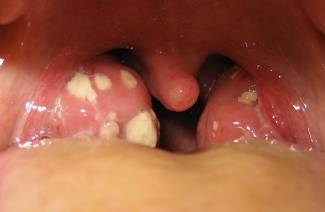

Bezler ağrıyor

Çocuklarda veya yetişkinlerde oluşan bezler - neden, tanı ve tedavi